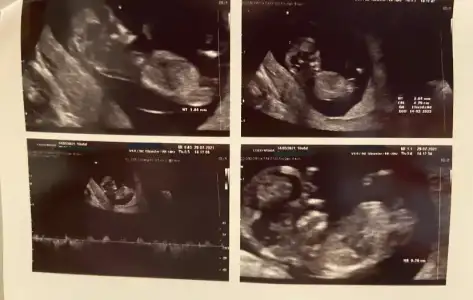

Kizim oluyor hayirlisiyla insallahEvet burada bacak arası boş görünüyor sağlıkla gelsin prensesdiğer usg de çıkıntısı vardı

renklide nub ölçümü olmuyor bakalım nolcak